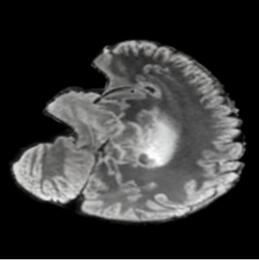

Our results unequivocally highlight the superior performance of X-Diffusion in terms of both qualitative and quantitative metrics. Representative MRI volumes generated by our pipeline, when juxtaposed with ground-truth images, showcased remarkable similarity, with even intricate physiological features like tumor information, spine curvature, and fat distribution being accurately captured.

Notably, X-Diffusion achieves sota dB for a few input slices while baselines require more than 60 input slices to achieve similar performance (Figure 7). The margin is more than 12 dB PSNR for the 1-slice input in both the BRATS and the UK Biobank benchmarks (see Table 1 and Figure 6). For reference, two randomly sampled MRIs from the UK Biobank would have a PSNR of 15.95 dB 0.36 (on 4800 randomly sampled examples). The slices from 3D reconstructed volumes at varying depths and axis of rotation visually match the ground truths (see Figures 5 and Figure 4). We also plot the error map (Figure 4) of such X-Diffusion generations to highlight the differences with the ground truth MRIs.

Tumour Information Preservation. For the brain tumor segmentation, we use a Swin UNETR model[27, 70], trained with random rotation, and intensity as data augmentation. In Figure 5, we highlight the tumor profiles of the generated MRIs compared to the ground truth tumour profile. In the test set with human ground-truth annotations (), the real MRI Dice score is 85.15 while the generated MRIs from a single slice have a dice score of 83.09. This shows how the generated MRIs indeed preserve the tumor information and can act as an affordable and informative pseudo-MRI, before conducting an actual costly MRI examination in hospitals.